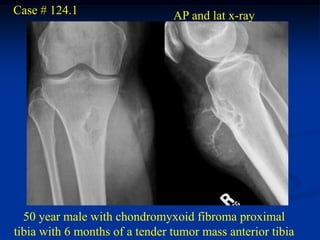

Case # 124.1                    AP and lat x-ray

50 year male with chondromyxoid fibroma proximal

tibia with 6 months of a tender tumor mass anterior tibia